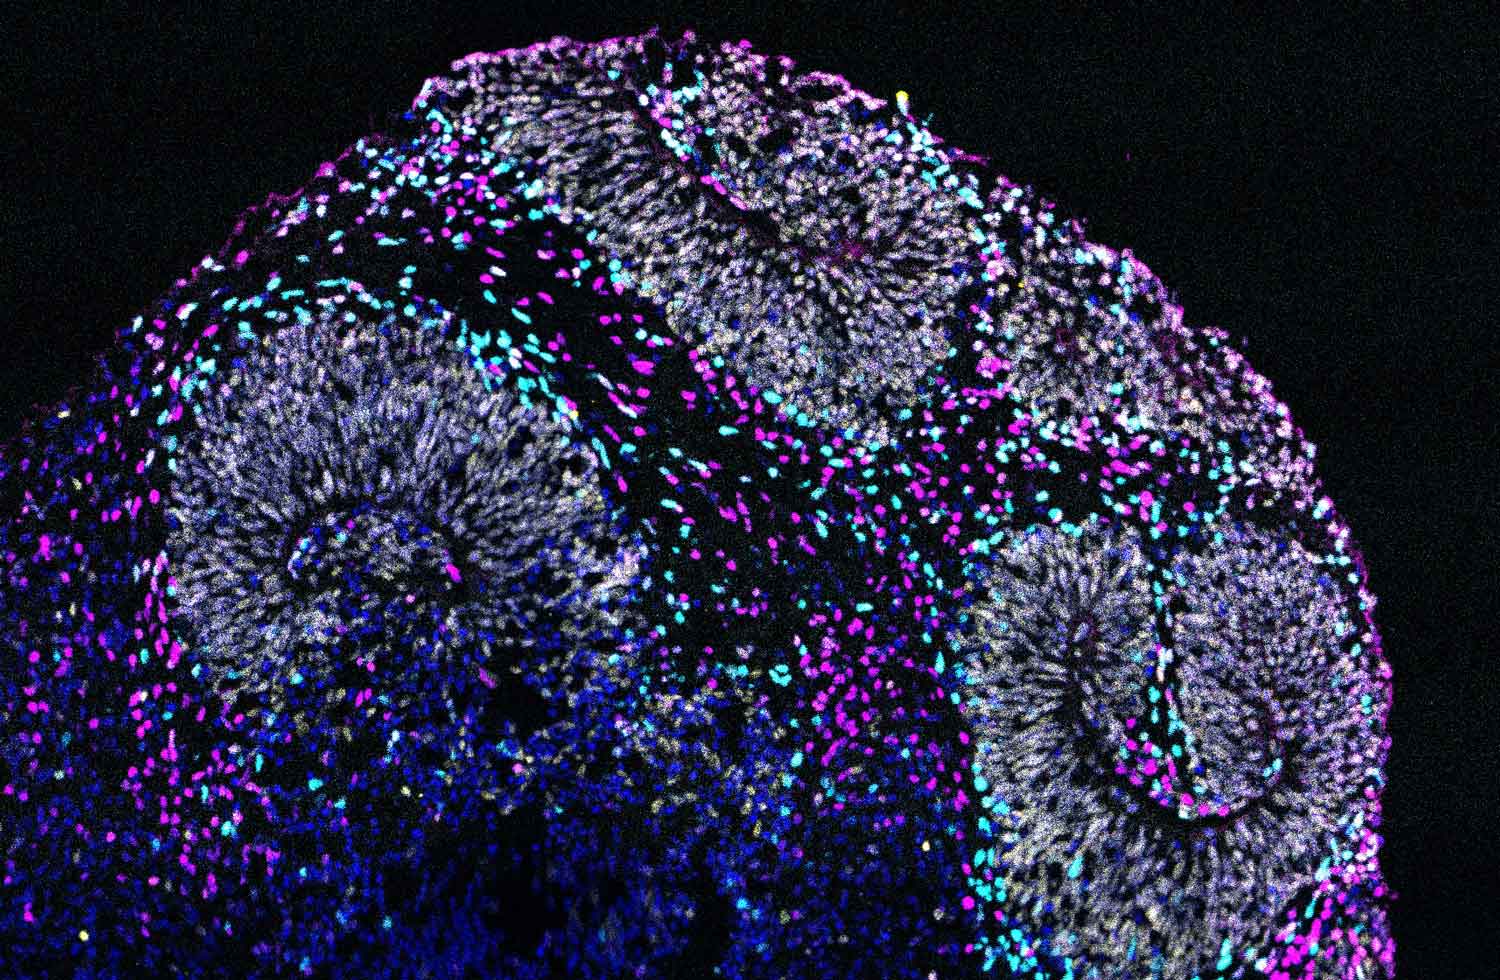

Microscope image of a brain organoid derived from human stem cells that contain a mutation associated with autism spectrum disorder.

Microscope image of a brain organoid derived from human stem cells that contain a mutation associated with autism spectrum disorder. These organoids are providing new insight into neurodevelopmental disorders. Image by David Shin, Nowakowski Lab

To look closely at the impact of one of these mutations, we introduced it into human stem cells using CRISPR, in collaboration with Tom Nowakowski, PhD, an associate professor of neurological surgery. Then we used those cells to grow what we call organoids, which are tiny bundles of cells that we can use to model what’s happening in a whole organ, in this case, the brain. Again, we saw defects in how the neurons were developing.

So, we were able to go from A to Z, from a set of genes connected to autism to being able to actually see, in this mini organ made of human cells, the biological effect a single mutation, and I think it could be done for many conditions beyond neuropsychiatric disorders too.